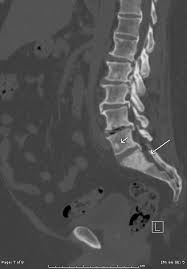

Metastatic Disease Of Spine Pathology Orthobullets

Metastatic Disease Of Spine Pathology Orthobullets from upload.orthobullets.com